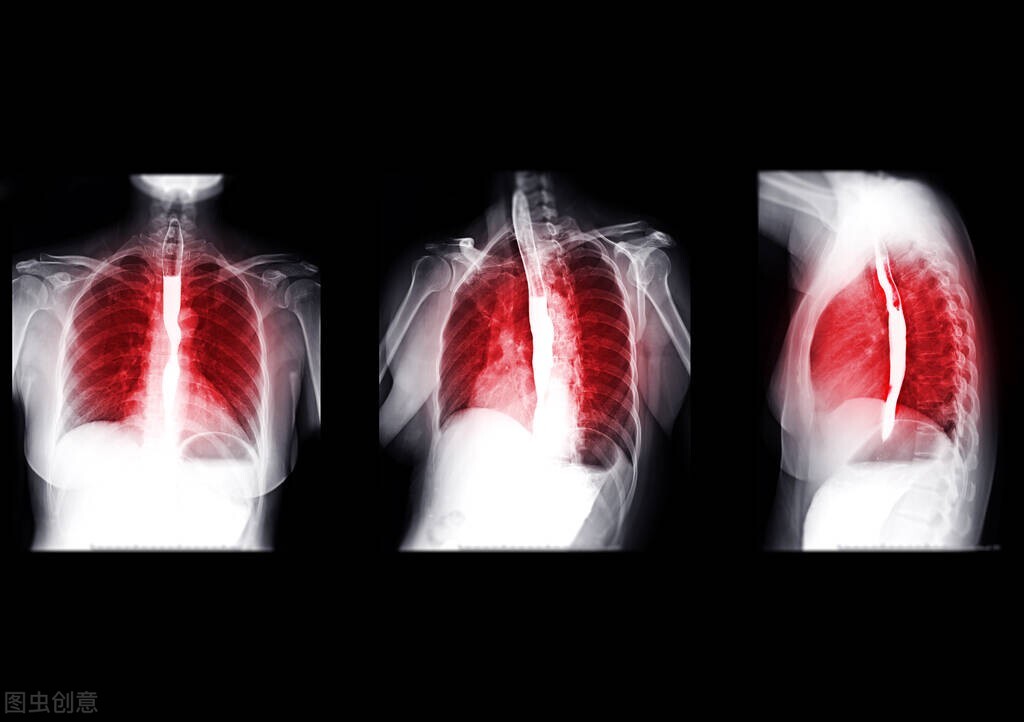

1、食道癌晚期有哪些痛苦的表现症状?

食道癌到了晚期,疾病的折磨是很痛苦的,主要症状有: